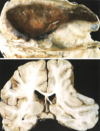

Enfermedad de Parkinson. A. Sustancia negra normal. B. Sustancia negra despigmentada en la enfermedad de Parkinson idiopática.

sustancia negra normal

perdida de sustancia negra - Parkinson